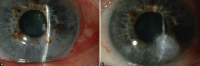

Corneal perforation is a potentially devastating complication that can result from numerous conditions that precipitate corneal melting. It is associated with significant morbidity and prompt intervention is necessary to prevent further complications. Causes include microbial keratitis, ocular surface disease, and autoimmune disorders and trauma. Various management options have been described in the literature to facilitate visual rehabilitation. This rview discusses the treatment options that range from temporising measures such as corneal gluing through to corneal transplantation, with decision making guided by the location, size, and underlying aetiology of the perforation.